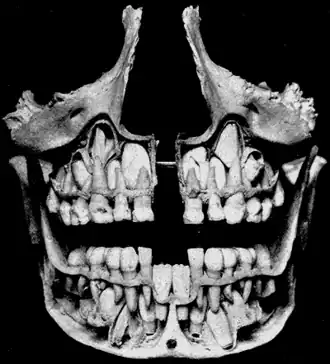

![]() Cross-section of upper and lower jaws with permanent teeth located above and below the deciduous teeth prior to their exfoliation. The deciduous mandibular central incisors have already been exfoliated. | |